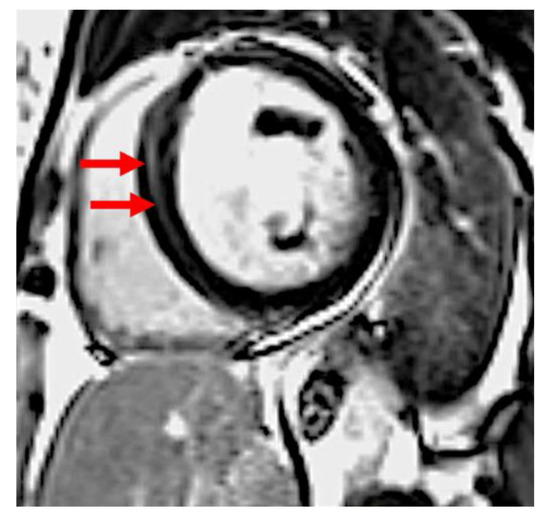

4.2. LV Fibrosis in PPCM

| LGE n (%) | 9 (43%) | 18 (60%) | 0.22 |

| LGE % (IQR) | 1.7% (0–2.9%) | 2.3% (0–4.5%) | 0.63 |